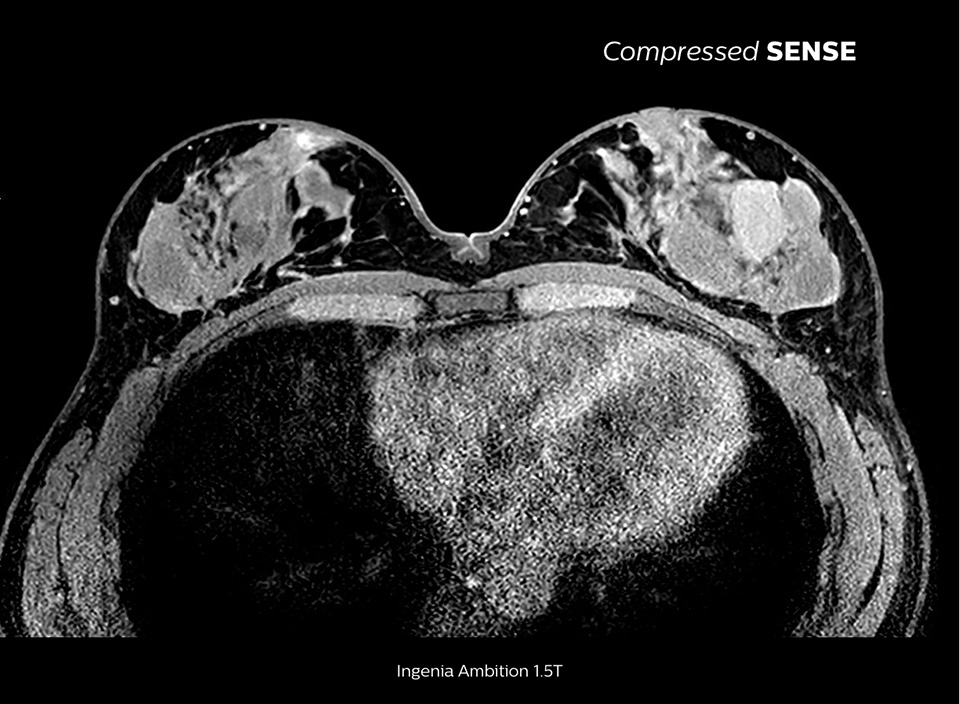

Up to 50% faster 3D sequences, with virtually equal image quality1

Compare the time savings of an MRI scan performed with Compressed SENSE MRI software versus a conventional scanning technique

A paradigm shift in productivity

Learn more about the main principles of Compressed SENSE MRI software and how it introduces a paradigm shift in productivity. Compressed SENSE was designed around image quality, and it can accelerate scans, increase spatial resolution and enhance the patient experience for clinical MR imaging.

High quality and fast scanning at KCH

The MRI staff at Kurashiki Central Hospital incorporated Compressed SENSE into most of the brain, spine, abdominal, and cardiac examination protocols on their Ingenia 1.5T, resulting in fast and high-quality MRI scans, which is welcomed by patients and staff.